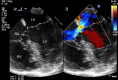

This review article will guide the reader through the basics of echocardiographic assessment of congenital left to right shunts in both paediatric and adult age groups. After reading this article, the reader will understand the pathology and clinical presentation of atrial septal defects (ASDs), ventricular septal defects (VSDs), atrioventricular septal defects (AVSDs) and patent arterial duct. Echocardiography is the mainstay in diagnosis and follow-up assessment of patients with congenital heart disease. This article will therefore describe the echocardiographic appearances of each lesion, and point the reader towards specific features to look for echocardiographically.